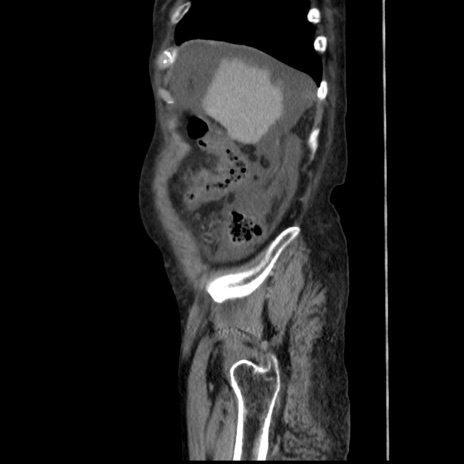

症例31(矢状断像)

【症例】80歳代 女性

【主訴】腹部膨満感

【現病歴】他院にて肝硬変にてフォロー中。1週間前から便秘、腹部膨満感、臍部腫瘤あり受診となる。

【既往歴】肝硬変

【身体所見】腹部膨隆あり、皮膚変化なし、疼痛なし。

【データ】WBC 4600、CRP 0.25